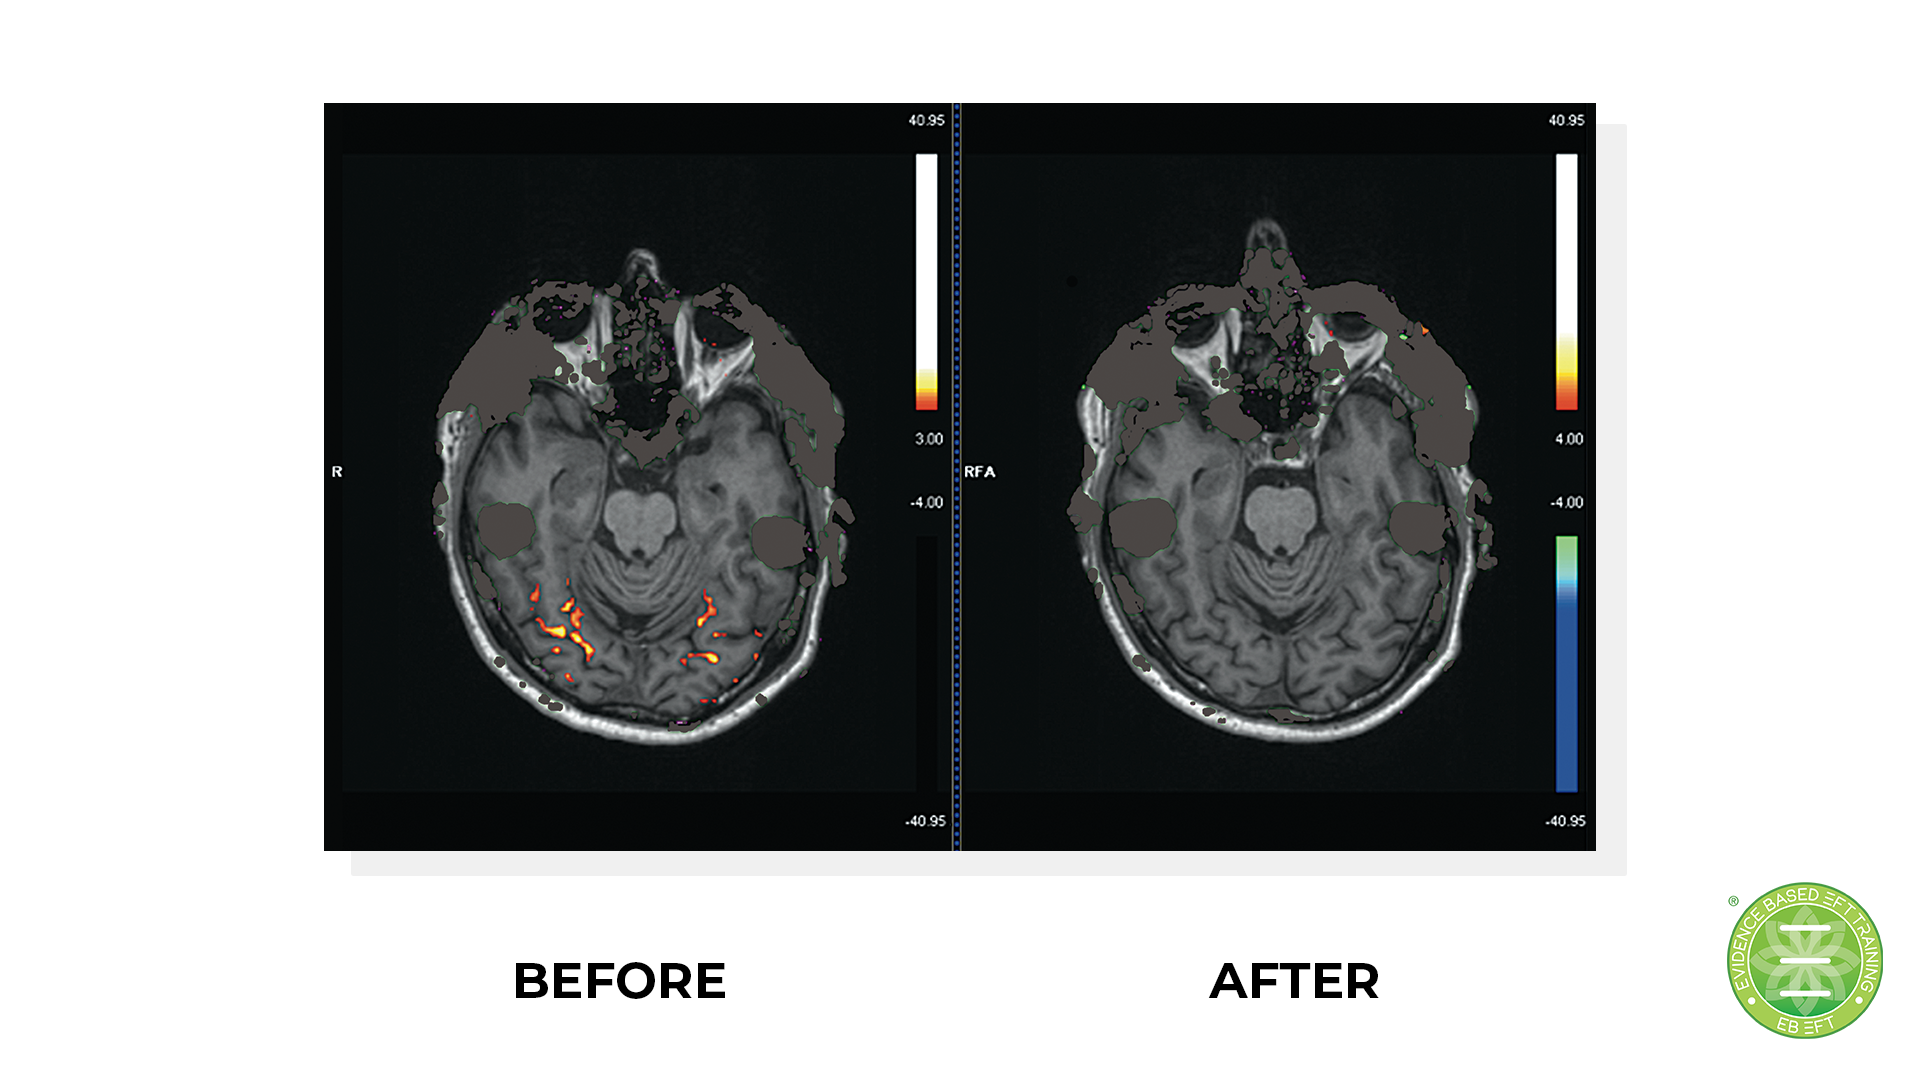

The Science of Tapping

Do you have doubts on if Tapping really works? In the following FREE VIDEO SERIES we explore the latest scientific based evidence that shows the tapping really does work.